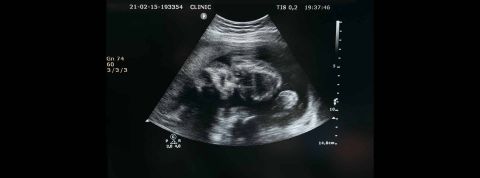

Selon un article publié dans la revue Cell, les scientifiques du département de génétique moléculaire de l'Institut Weizmann à Tel Aviv ont créé les premiers « embryons synthétiques » au monde, sans sperme ni ovule, mais à partir de cellules-souches. Une première mondiale selon le comité de lecture de la revue.

Connues sous le nom d'embryons synthétiques parce qu'elles sont créées sans œufs fécondés, les structures vivantes devraient permettre une meilleure compréhension de la façon dont les organes et tissus se forment lors du développement des embryons naturels. Les chercheurs pensent que ces travaux pourraient réduire l'expérimentation animale et ouvrir la voie à de nouvelles sources de cellules et de tissus pour la transplantation humaine. Interrogé par The Guardian, le professeur Jacob Hanna, biologiste à l'Institut Weizmann, déclare : « L'embryon est la meilleure machine à fabriquer des organes et la meilleure bio-imprimante 3D - nous avons essayé d'imiter ce qu'il fait. »